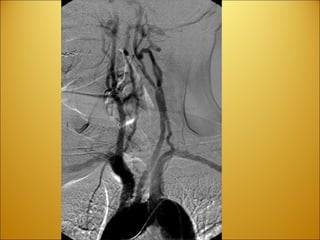

Stroke Ischemic Vs. Hemorrhagic CVA vs TIA Aneurysm Berry @ Basilar/Posterior cerebral  artery SAH

Stroke Ischemic Vs.Hemorrhagic CVA vs TIA Aneurysm Berry @ Basilar/Posterior cerebral artery SAH